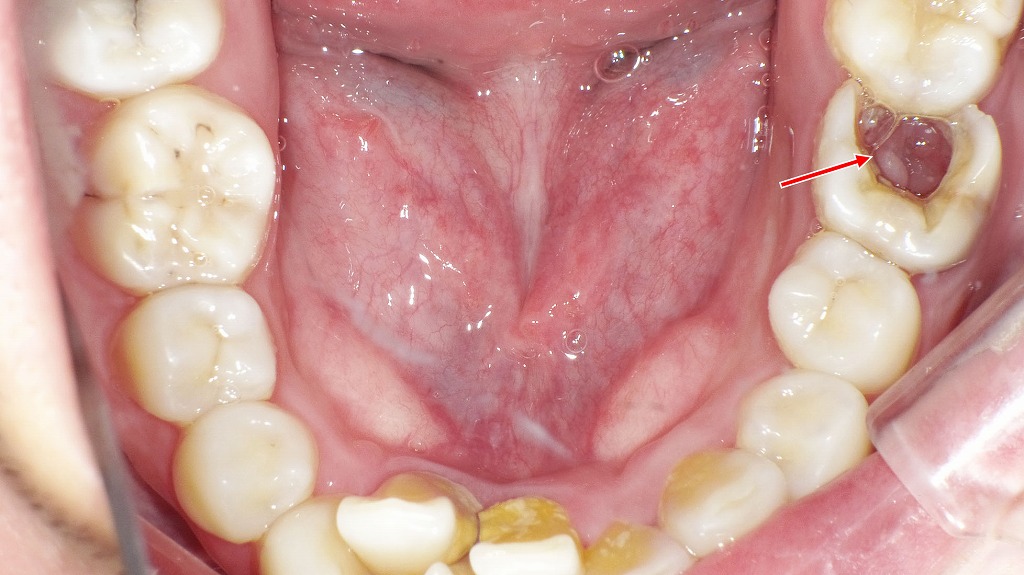

下顎6番の重度虫歯 ― 口腔内所見とレントゲンから抜歯に至った症例

下顎6番(第一大臼歯)に大きな欠損が認められ、口腔内写真では歯質が大きく崩壊している状態が確認できます。レントゲン画像では、虫歯が歯冠部から歯根深部まで進行し、歯根周囲の骨吸収および根尖部の透過像が明瞭に認められました。保存治療による改善が困難と判断され、感染源の除去と周囲組織の回復を目的として抜歯が適応となった症例です。